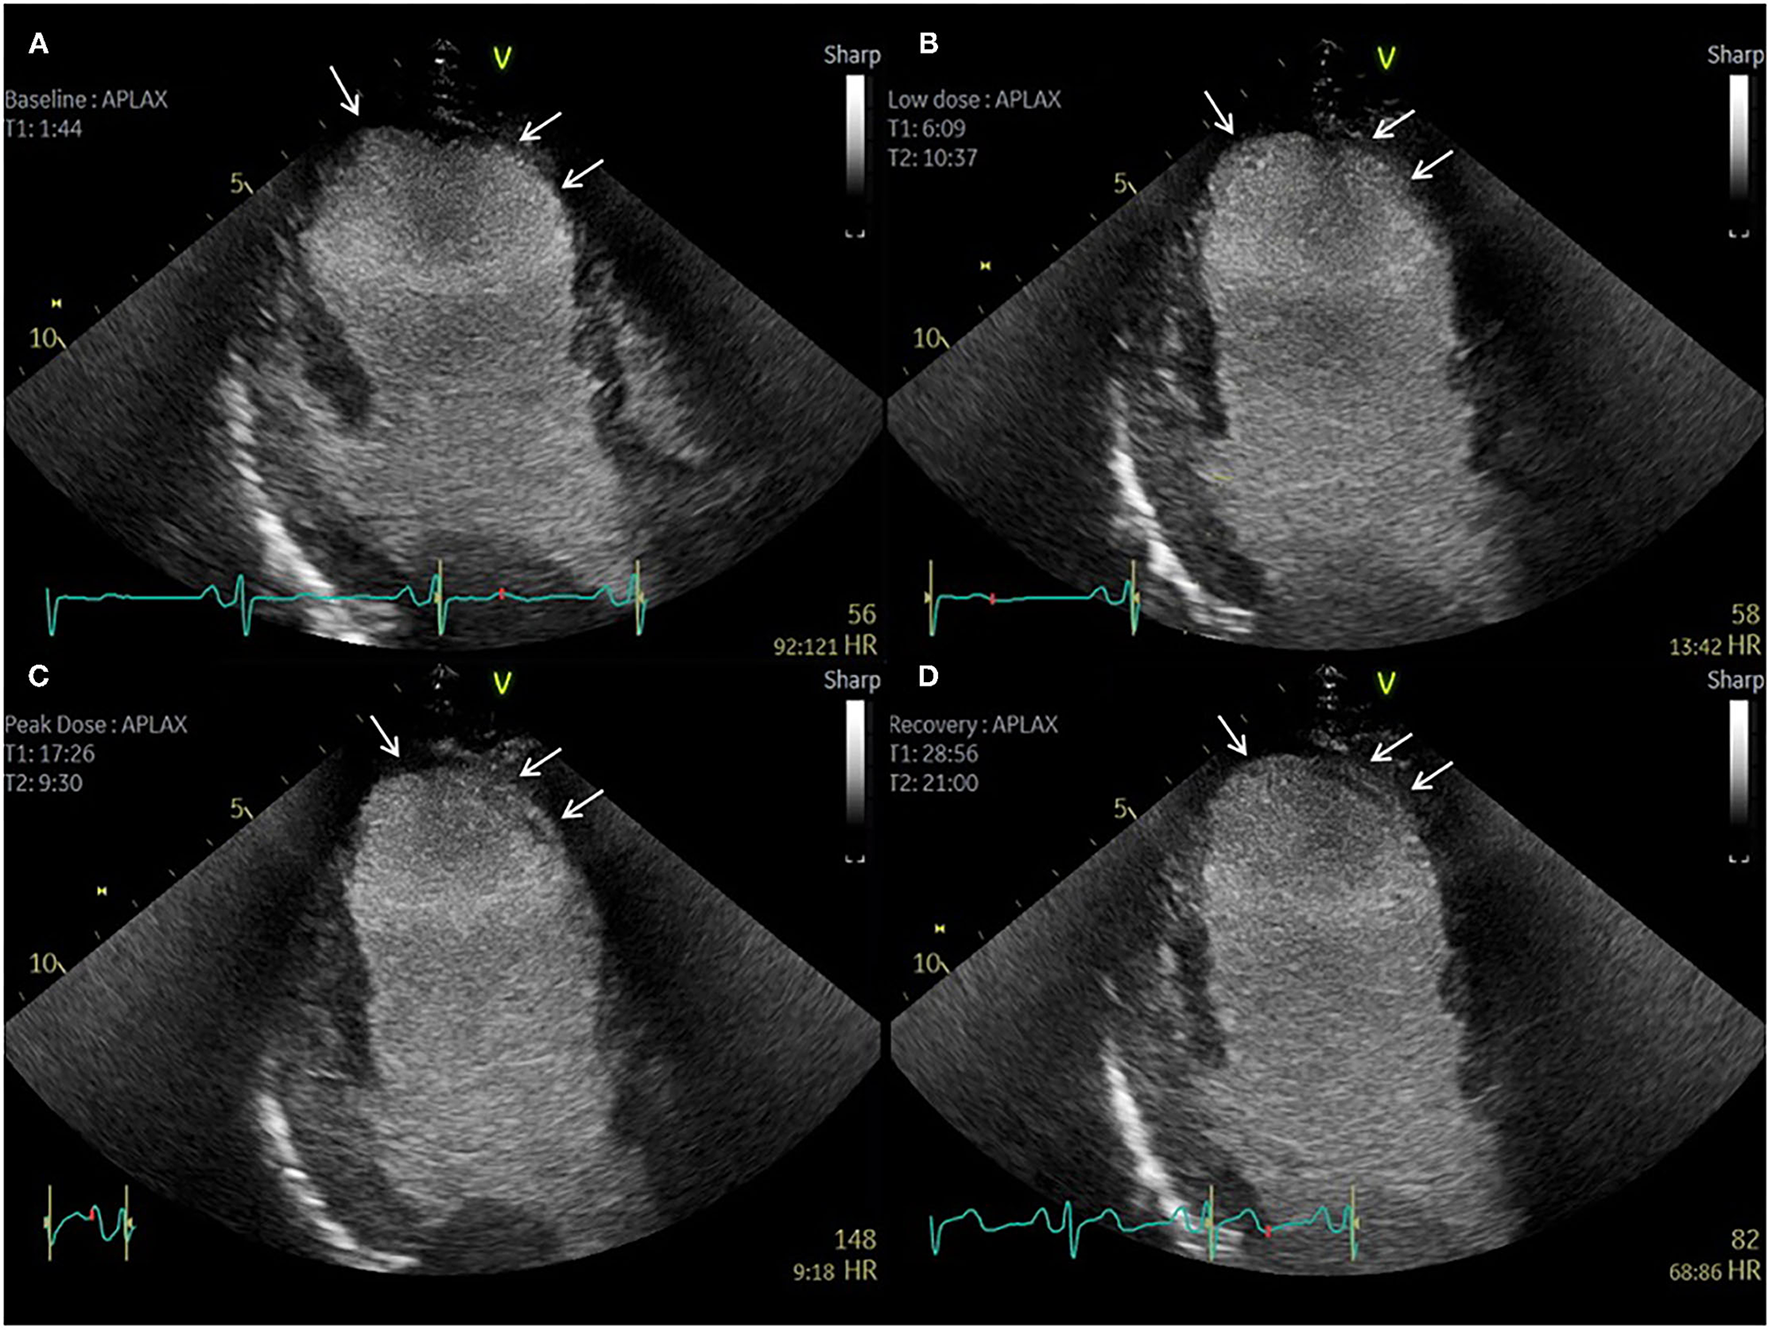

Evidently, imaging modalities that can provide simultaneous evaluation of ischaemia and tissue characterization can be advantageous in these circumstances, more so in cases of extensive or complex anatomical scar. Similarly, imaging modalities capable of providing complete LV coverage such as PET and SPECT enable a more comprehensive assessment of the relation between ischaemia and scar in this context, particularly when paired with anatomical data (Figure 2). Despite this, echocardiography remains the most widely used modality for evaluation of relative differences in wall motion, and often enables accurate evaluation of the extent of regional viability and ischaemia, particularly when facilitated by contrast echocardiography (Figure 5) (58). It is worth noting that a recent expert consensus statement on the use of multimodality of myocardial viability, makes no recommendations on a preferred imaging modality in this population (59), further highlighting the complexities in the evaluation of patients with prior CABG.

Figure 5. Contrast echocardiography post coronary artery bypass graft surgery. Sixty-three-year-old patient with previous CABG and atypical chest pain. (A–D) Apical 3 Chamber view. Baseline, low dose, peak dose, and recovery stages, respectively. Contrast Enhanced Images. Akinetic mid and apical antero-septal wall segments (arrow). No improvement in contractility of these segments during low dose stage confirms non-viable segments. Improvement in contractility of all other segments during low dose and peak dose suggests the presence of viable myocardium and no inducible ischaemia.